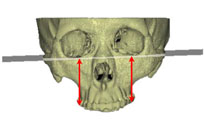

그림 2. 안면비대칭을 주소로 내원한 23세 남자환자로서 골격성 3급 부정교합과 함께 좌측의 반대교합을 보여주고 있다. menton이 심하게 좌측으로 편위되어 있어 우측과두가 좌측에 비해 과성장한 것에 의해 나타난 RM type의 안면비대칭으로 보여졌다.

그림 3. 정모두부방사선사진의 투사도를 작성하고 분석을 시행한 결과 Me은 편위된 반면 ramus length의 좌우차이는 보이지 않아 기계적으로는 M type으로 판정되었다. 그렇다면 본 환자의 이부편위는 어떻게 나타났는가?어느 부위의 좌우차이가 본 환자의 이부편위에 기여하였는지 2차원적인 방사선사진만으로 잘 파악이 되지 않는다.